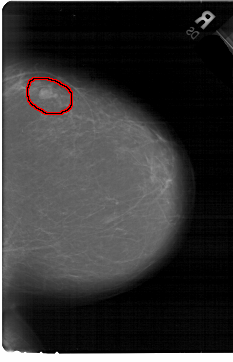

A_1440_1.LEFT_MLO

FILE: A_1440_1.RIGHT_MLO.OVERLAY

TOTAL_ABNORMALITIES 1

ABNORMALITY 1

LESION_TYPE MASS SHAPE LOBULATED MARGINS CIRCUMSCRIBED

ASSESSMENT 4

SUBTLETY 4

PATHOLOGY BENIGN